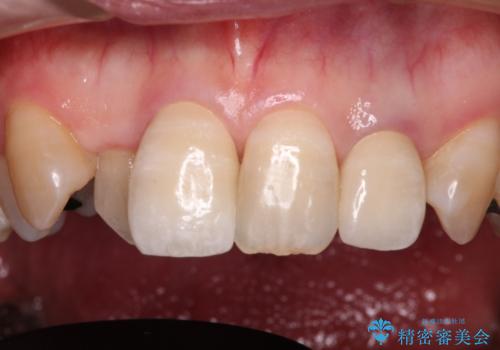

- 20年以上前に神経を取り除いた前歯の変色が気になるとのことで来院された患者様です。

レントゲン写真より、歯根の炎症が認められなかったため、ファイバーコアによる土台築製後、オールセラミッククラウンにて補綴することとしました。

また、真ん中の前歯はコンポジットレジンによる修復跡が目立っており、合わせてオールセラミッククラウンにて治療することとしました。

歯に独特の縞模様があり、さらに特徴的な色合いであったため、コンポジットレジンによる修復では対応が困難でした。

オールセラミッククラウンは周囲の歯よりもやや白く製作し手降りますが、今後はご自身でホワイトニングをして明るい色調で整えるとのことでした。